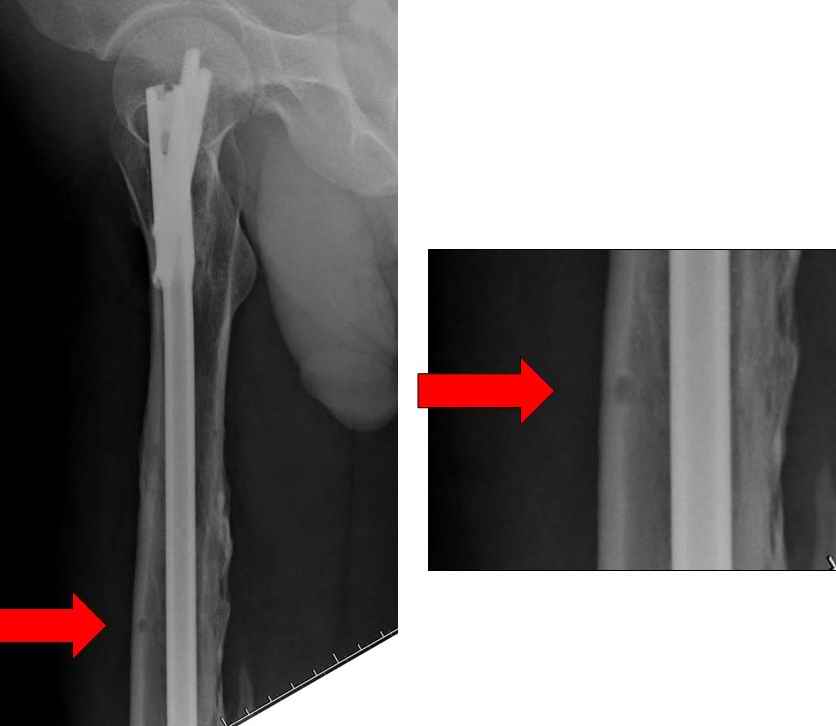

Мы не дождались “Happy End”, у больного IQ в пределах 70%, через 6 месяцев вернулся после небольшой травмы, споткнувшись получил перелом

того же бедра (рис №7).

При обзоре причин перелома, на снимке №2 обнаружили, что один из стержней аппарата наружной фиксации проходил только через передний кортекальный слой, что создало стрессовую зону на бедре и в результате перелом из-за незначительной травмы.

На снимке N2 виден канал от стержня во фронтальной плоскости, на уровне которого на снимке N7 уже перелом.

Снимок №4 сделан после несостоятельности интрамедуллярного штифта, осложнения инфекцией канала и после миграции шурупов. Я имел ввиду, что снимок № 2 после удаления наружного фиксатора в интрамедуллярном варианте, на увеличенном снимке дырка на переднем кортексе (см. снимок) stress zone Чтобы правильно без осложнений провести half pins, необходимо соблюсти нескольких правил, во первых, они должны вводится в середине диаметра кости с предварительным просверливанием. Во время просверливания кости, сверло проходит первый, потом второй дальний кортекс и стержен вводится вручную. А иногда сверление проходит по касательной к кортексу, нагреваются местные ткани, создается ожог и локальный некроз. Или как будто делается кортикотомия с помощью сверла, как при

методе Илизарова, ослабляя кортикальный слой. Создается стрессовая зона, которая при незначительной травме может осложниться стрессовым

переломом.